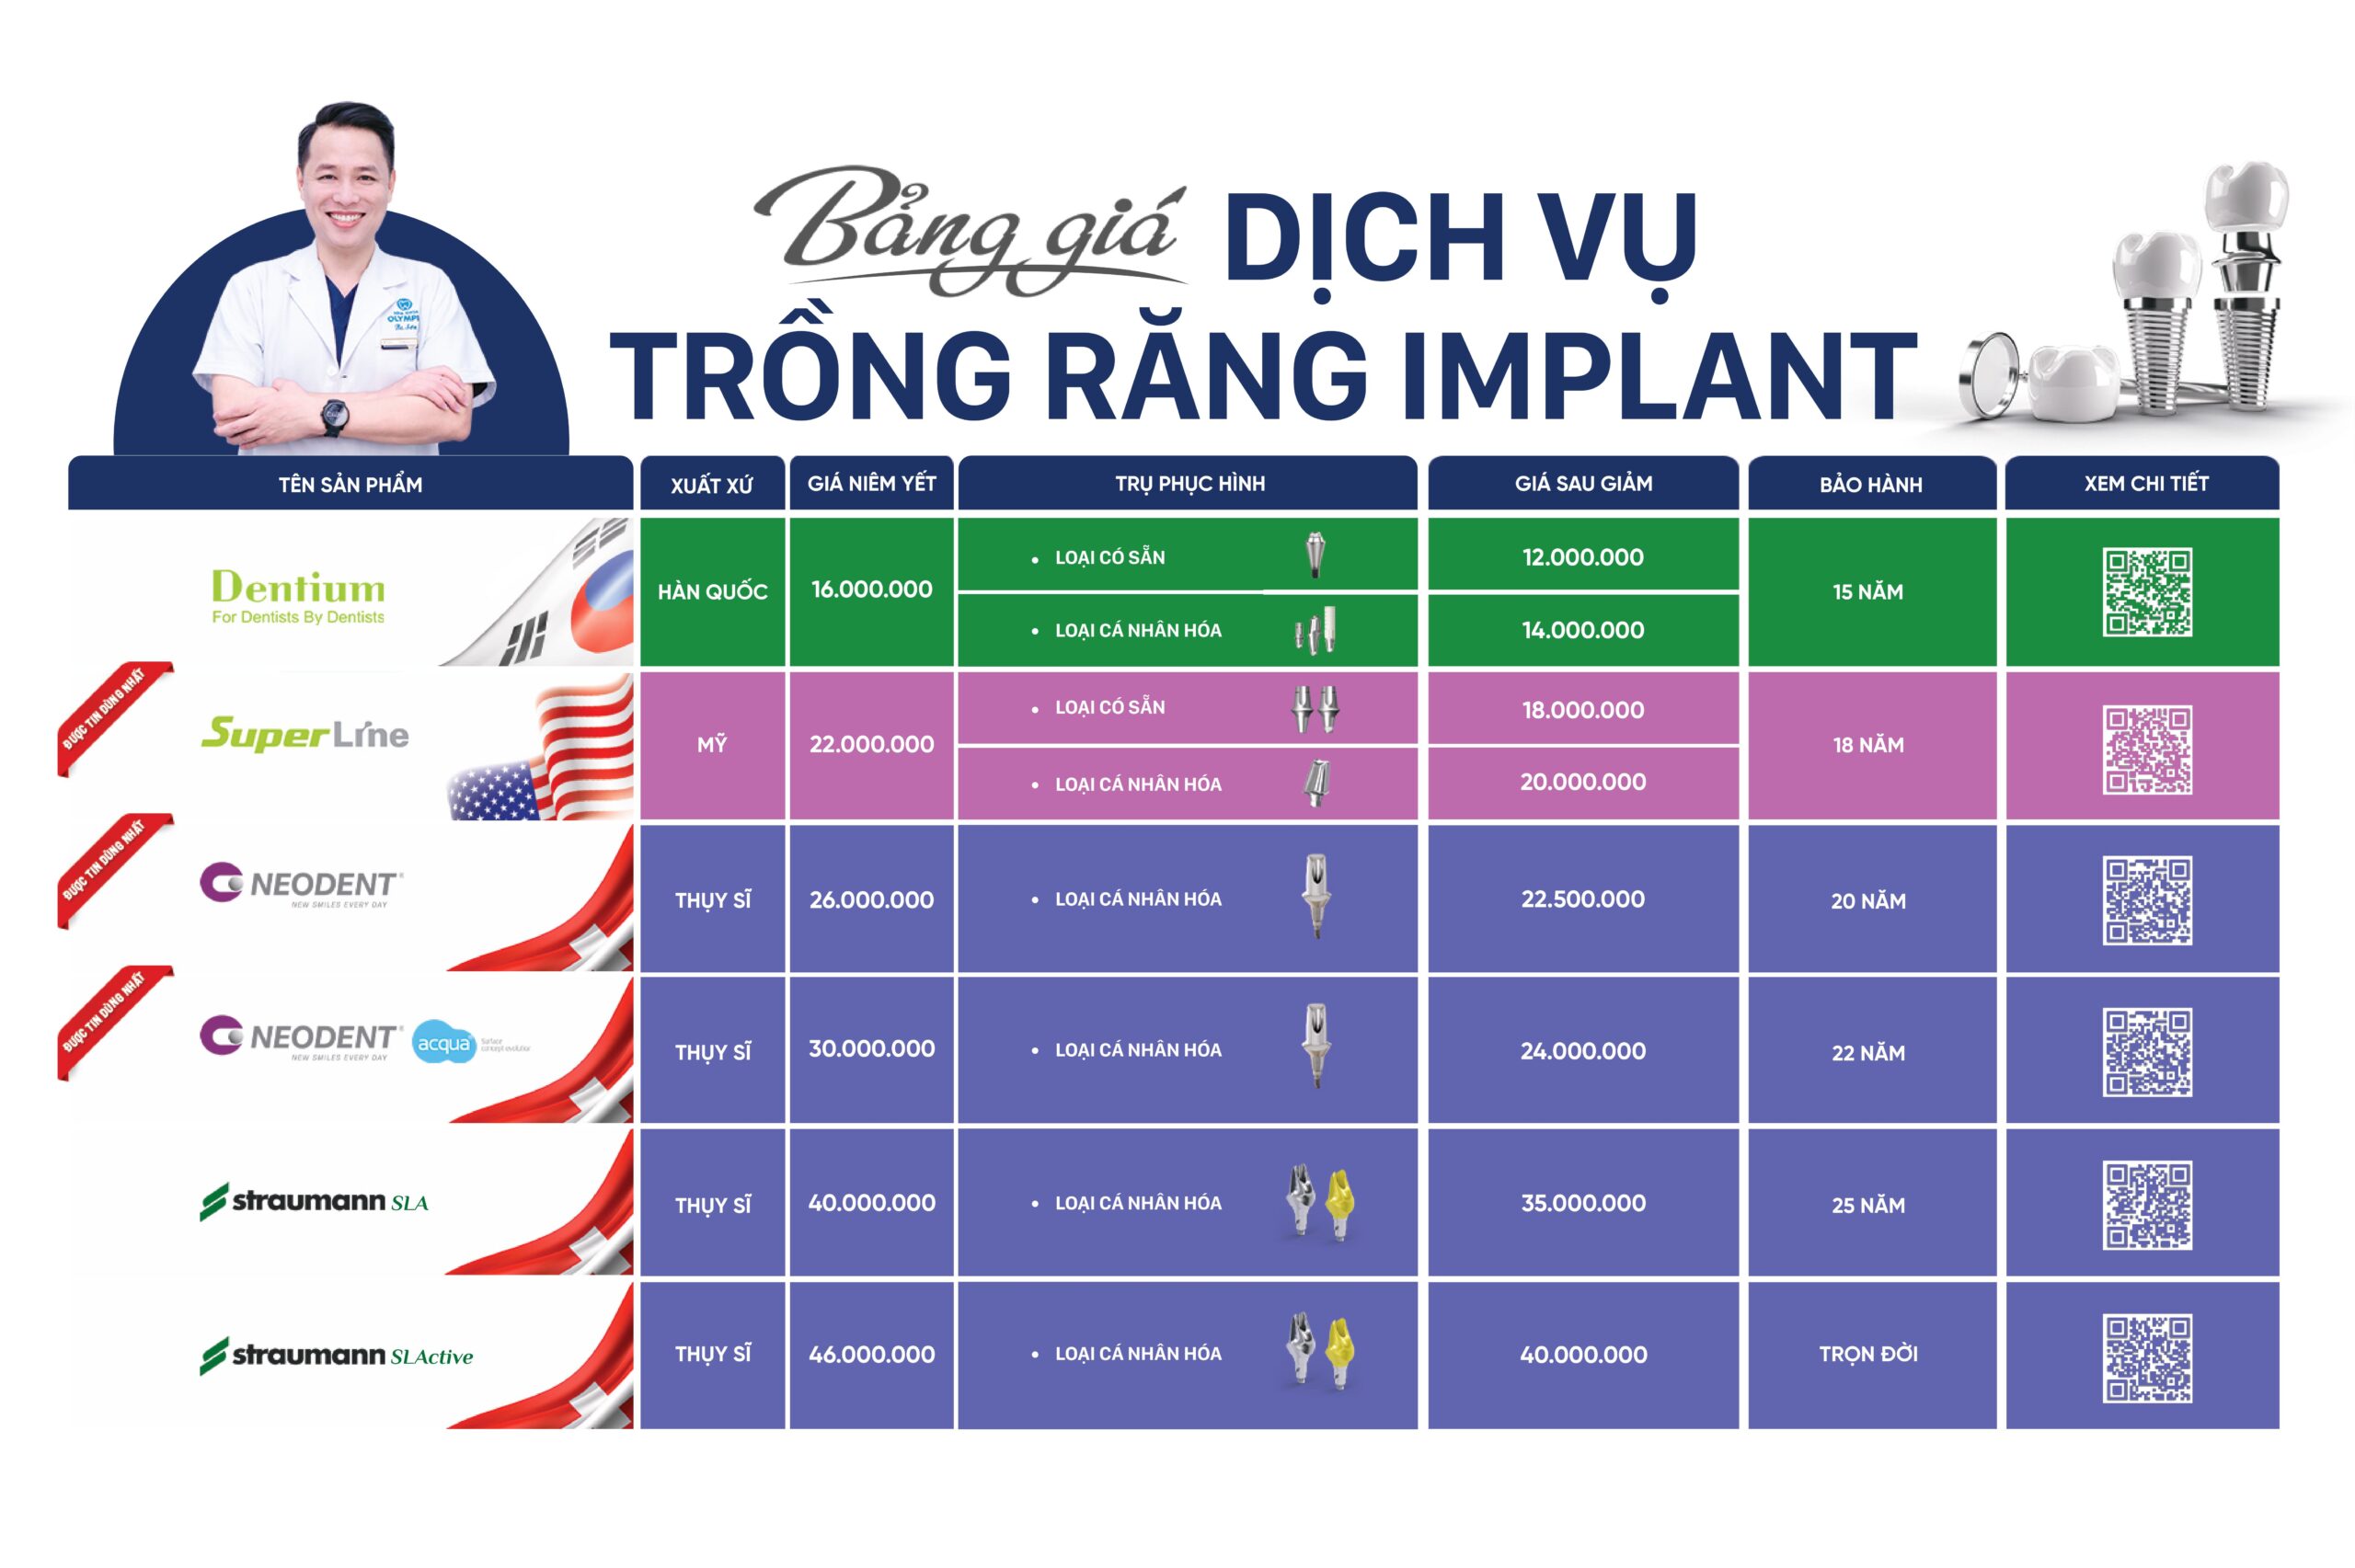

- Chi phí trụ Dentium (1 chân trụ Implant, trụ kết nối có sẵn, mão răng sứ kim loại): 12.000.000 – 15.000.000 VNĐ

- Chi phí trụ SuperLine (Chân trụ Implant + 1 abutment có sẵn + Mão răng toàn sứ) : 18.000.000 – 20.000.000 VNĐ

- Neodent (Chân trụ Implant + 1 abutment cá nhân hóa + Mão răng toàn sứ): 22.500.000 – 24.000.000 VNĐ

- Straumann SLA (Chân trụ Implant + 1 abutment cá nhân hóa + Mão răng toàn sứ): 35.000.000 VNĐ

- Straumann SLActive (Chân trụ Implant + 1 abutment cá nhân hóa + Mão răng toàn sứ): 40.000.000 VNĐ